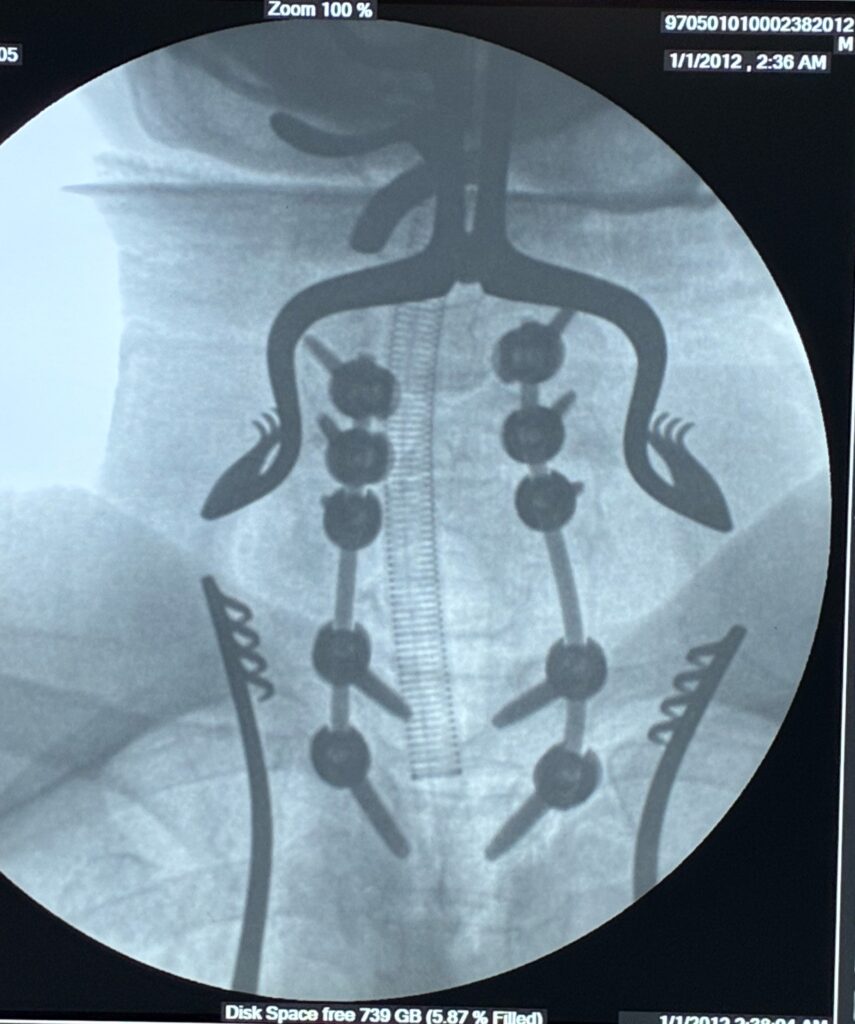

4. Surgical Treatment

Surgery is one of the most common treatments for spinal cord tumors, especially when the tumor is pressing on nerves or causing weakness.

Surgical goals include:

• Removing the tumor safely

• Relieving pressure on the spinal cord

• Preserving nerve function

Modern spine surgery uses advanced techniques and microscopes, which allow precise tumor removal with less damage to surrounding tissues.

Cases treated by Spine Specialist Dr. Gaurav Sandeep Gupta